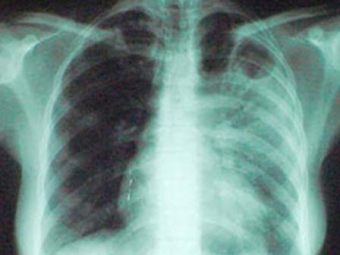

Головний лікар обласного протитуберкульозного диспанеру Віталій Дідик, закликає жителів області протягом місяця пройти флюорографічне обстеження в поліклінічних відділеннях закладів охорони здоров’я області.

Всього в рамках місячника планується охопити профілактичними флюорографічними оглядами близько 50-ти тисяч жителів області.